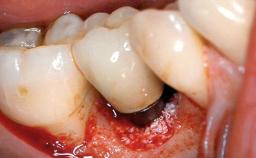

Peripheral Giant-cell Granuloma Associated with Peri-implant Tissues

Placement Protocol Early or late implant placement